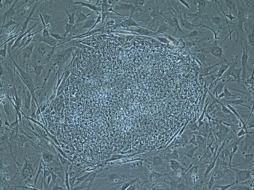

Tecnología Científico que clonó células madre embrionarias admite errores 23 de mayo de 2013 - 21:44 hs Ciencia médica Células madre

Tecnología Extraen células madre de embriones clonados 16 de mayo de 2013 - 01:03 hs Ciencia médica Células madre